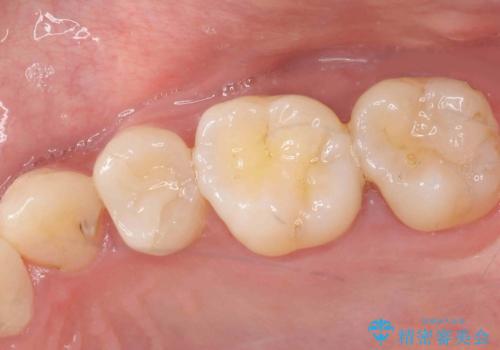

歯のガタつきも解消することができました。

e-maxクラウンでは仮着ができませんが、今回は一回でご満足いただける修復ができました。